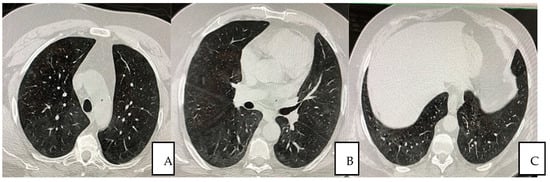

The patient was treated with autologous plasma and stem cells. He was not a smoker; he was overweight, with pre-existing medical conditions such as asthma, seasonal allergy and hypertension. He received the same protocol treatment as the other hospitalized patients as per the “SG Moscati Hospital” guidelines, composed of antiviral agent, steroid, anticoagulant and antibiotic agents. The protocol previewed 12 applications until the complete resolution of the patient. Autologous plasma administered between the day 1 and 22 days after the admission showed no collaterals, rejection or adverse events. The viral load was undetectable at day 10 in the hospital and any severe side effects were observed thoroughly the whole treatment period afterwards. At day 12, the patient was dismissed and the treatment continued on weekly bases each time measured by Complete Blood Count (CBC) analysis. Typical CT imaging of COVID-19 includes bilateral, apical, parenchymal, peripheral, and basal predominant ground-glass opacity and consolidation. The CT shows that at day 35, with a total of five plasma transfusions, the damages had been reduced by 98% (Figure 2A–C).

Figure 2.

(A–C) Pulmonary HRCT scan obtained on day 35 from symptom onset (23 December 2020) shows almost complete resolution of the initial presentation.